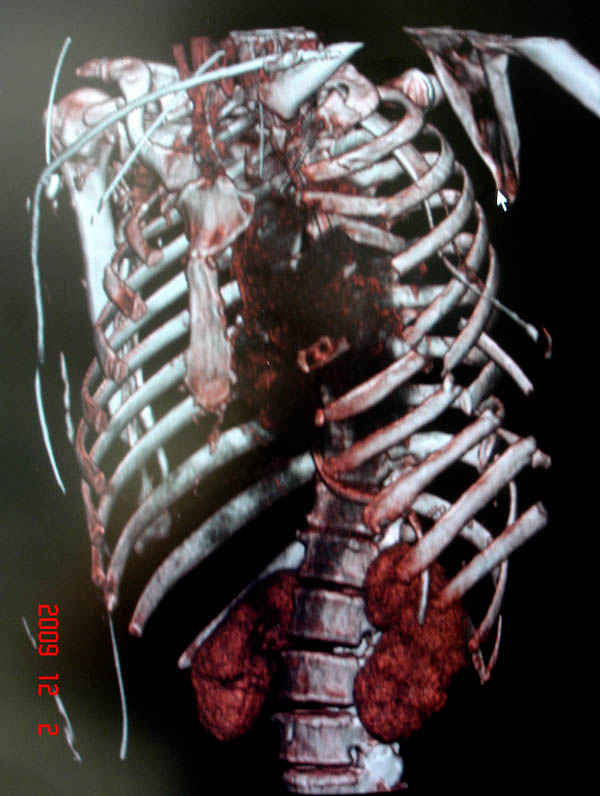

К нам поступила больная 56 лет после автоаварии в бессознательном состоянии, которая срочно заинтубирована в приемном отделении и сделаны необходимые исследования. Данные КТ и рентген показали перелом дистального бедра и Dissociation upper extremity - закрытый отрыв левой верхней конечности на уровне грудинно-ключичного сочленения и множественные переломы ребер.

На седьмые сутки нами совместно с торакальным хирургом сделана операция по фиксации грудинно-ключичного сочленения и переломов ребер.

Не все переломы ребра фиксированы, и поэтому хотели услышать комментарии тех, у кого имеется опыт.

В основном переломы ребер мы тоже не фиксируем, но учитывая, что в данной презентации, кроме разрыва грудинно-ключичного сочленения, дополнительно имелись множественные переломы ребер, некоторые сегментарные. После такой травмы трудно восстановить функцию западающей грудной клетки, и поэтому после дисскуссии с торакальным хирургом мы коллективно приняли решение зафиксировать переломы ребер тоже.

Отмеченный Александром случай из России заинтриговал меня давно и как раз выдался случай..., тем более новый имплант от Synthesа в 1.5 мм отвечал всем требованиям остеосинтеза ребер.